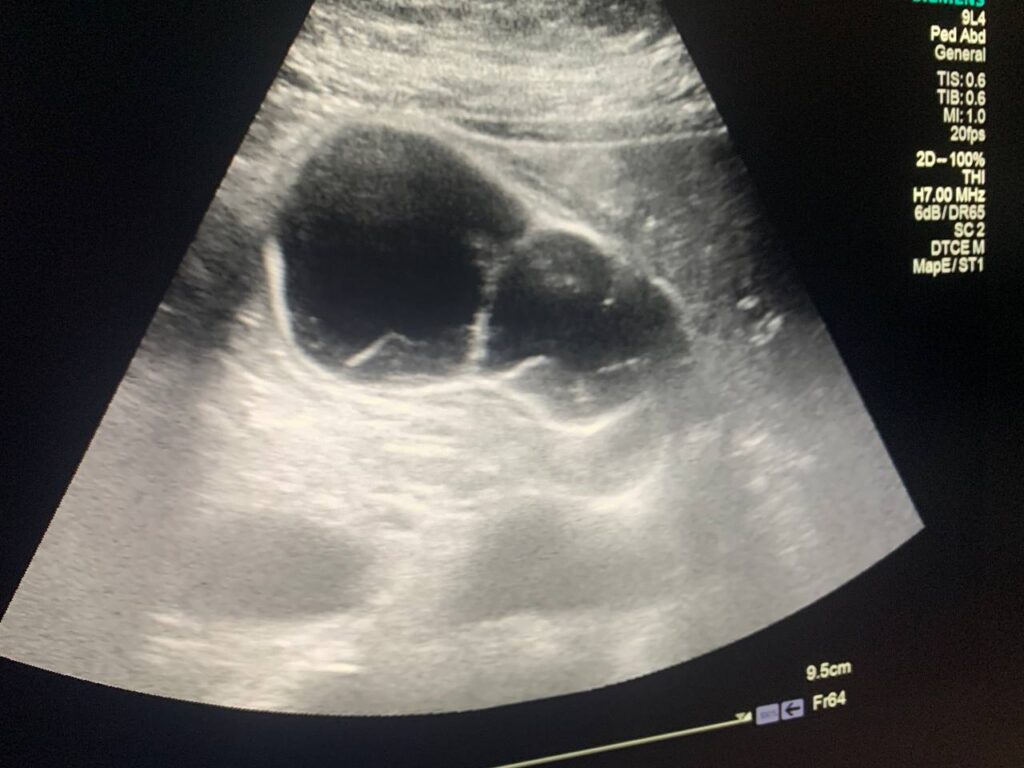

U/S : Gall bladder : distended , contain stone 9mm , full with heterogenous fluid , contain multiple honeycomb septations , also associated with pericholecystic edema 3.5mm , picture mostly of acute on chronic cholecystitis , please for further study normal common bile duct